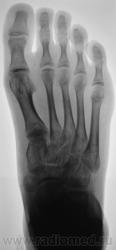

Травмы не было. Боли в стопе.

Головка 2 плюсневой кости уплощена-остеохондропатия..Не совсем понятно уплотнение структуры основания 1 плюсневой кости-может быть для такого возраста это норма?.Зоны роста видны.

Вторая болезнь Кёлера?

+ за свежий Келлер 2

болезнь Кёлера.